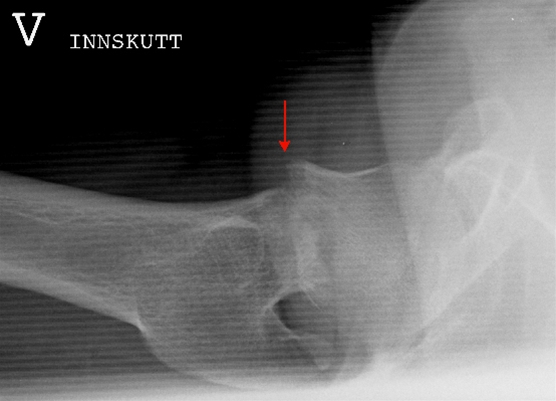

Collum femoris fraktur, sideoptagelse

Røntgen sideoptagelse af venstre hofte med medial collum femoris fraktur, der er forskudt (pil) og bagudvinklet.